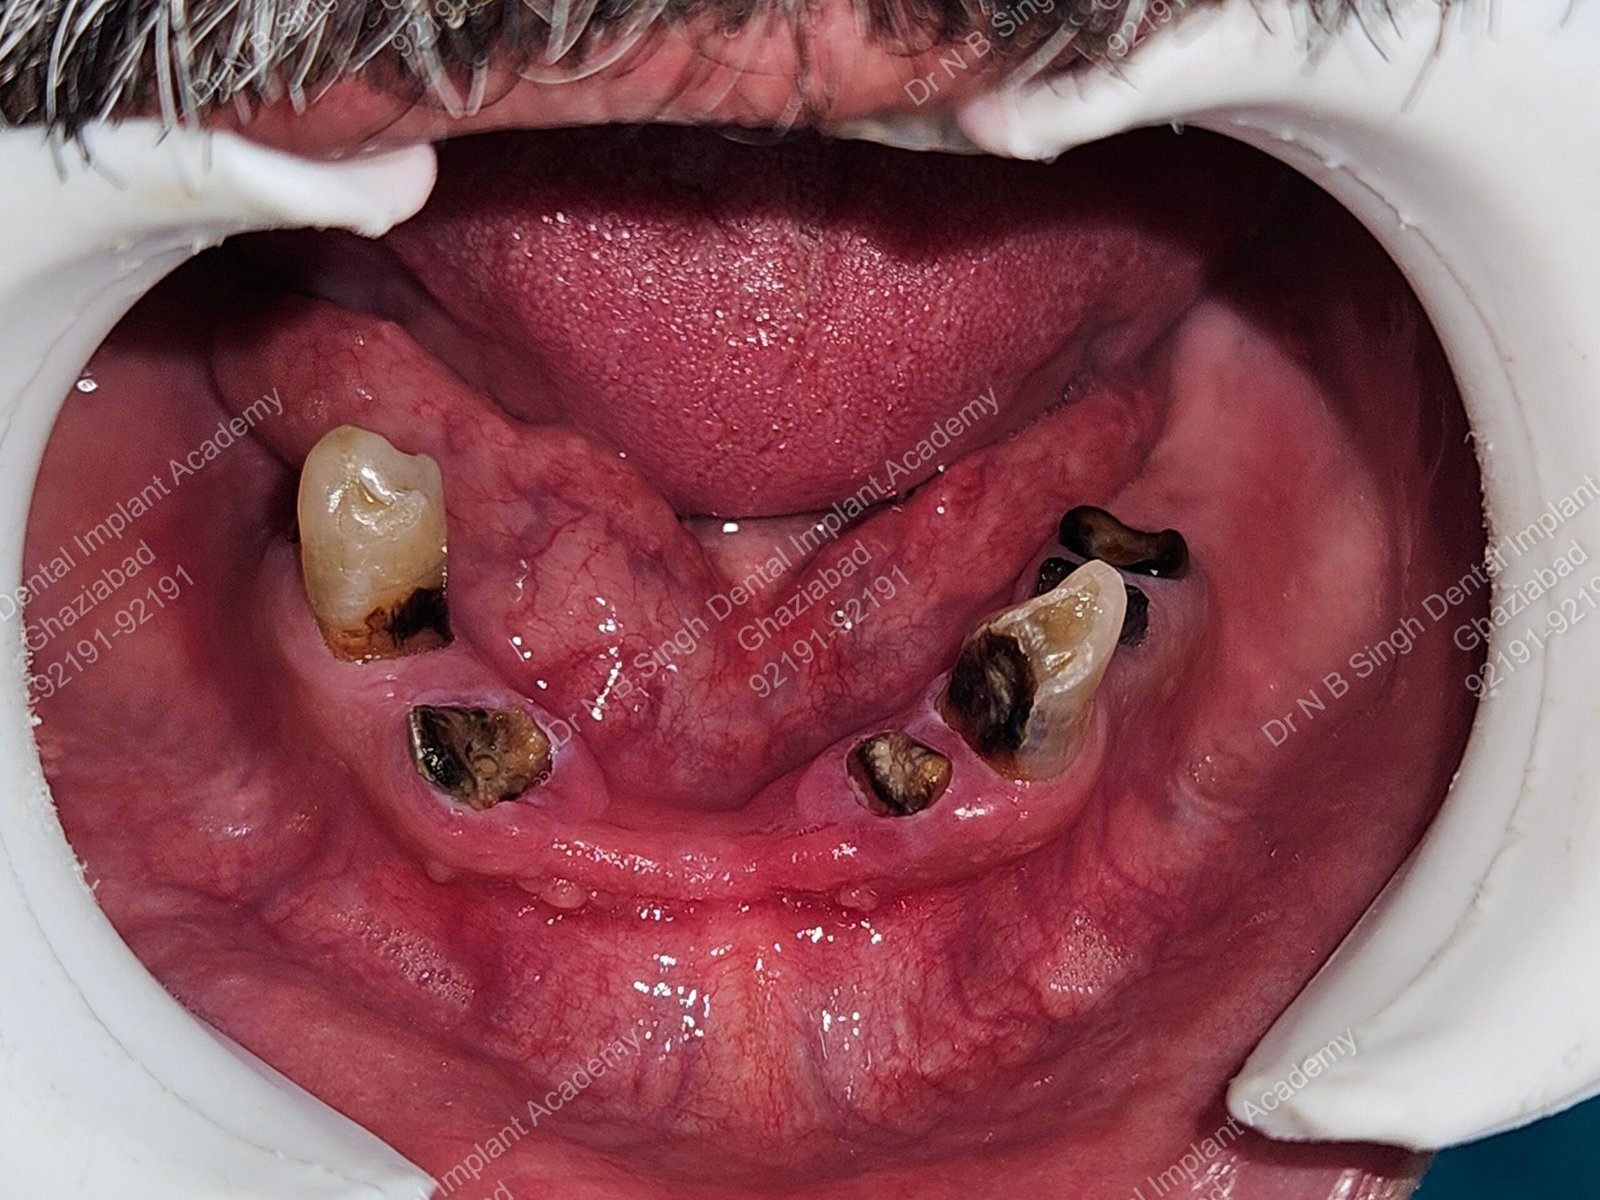

1006 Basal implant full mouth-DEEPAK